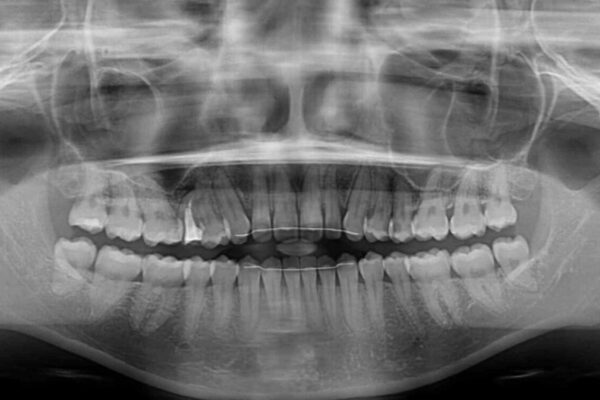

治療前

• 隙間だらけの歯列 インビザラインで改善 治療前画像